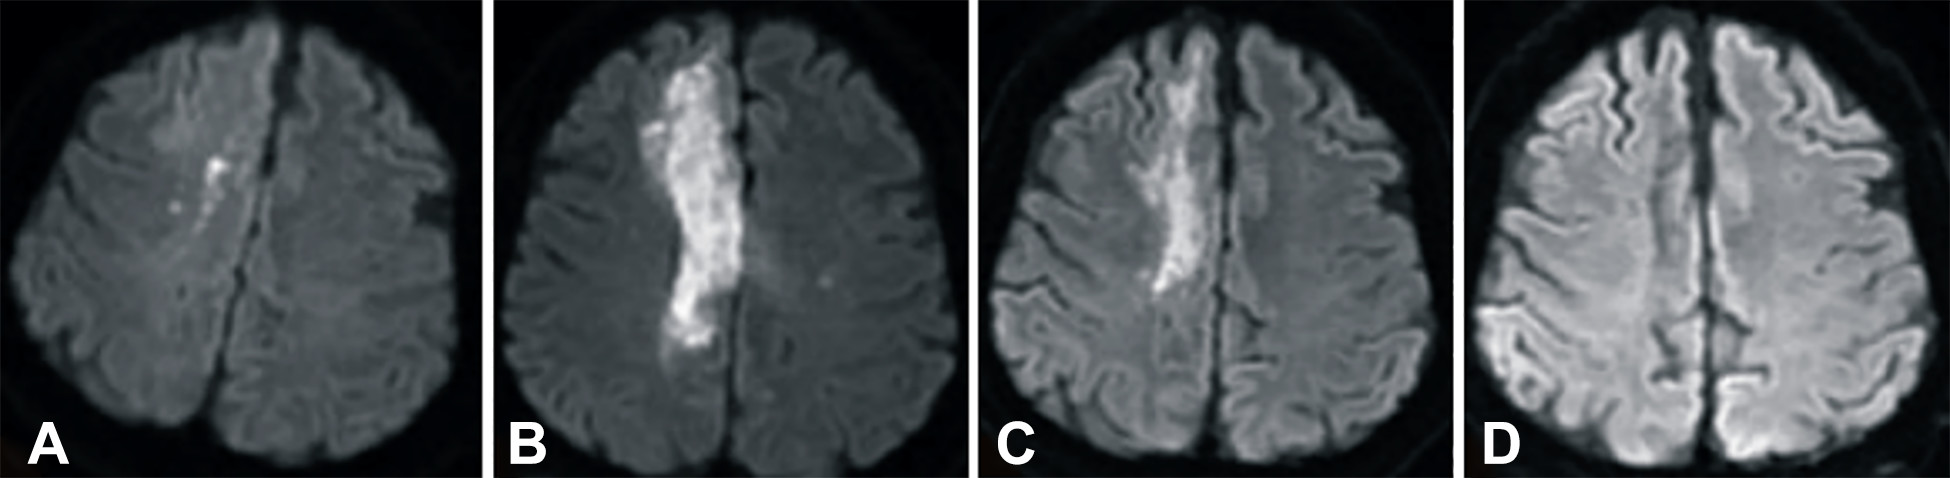

發(fā)病后2小時和8天行彌散加權(quán)成像(DWI)檢查,發(fā)現(xiàn)右側(cè)放射冠梗塞(白色信號增加),3個月后梗塞散在,6個月后消失(圖2A-D)。